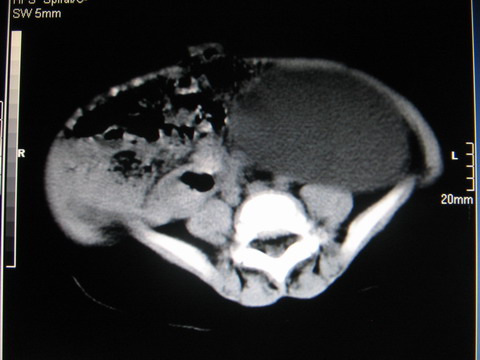

标题: PED0552:男1岁,双肾区CT

胎龄5个月时b超示左肾积水,现一岁后复查

左肾重度积水!

左肾重度积水!考虑肾盂输尿管交界处先天性狭窄或闭塞所导致

左肾重度积水.

左肾重度积水。

左肾重度积水(先天性左输尿管狭窄所致?)。

先天性左输尿管狭窄所致左肾重度积水。